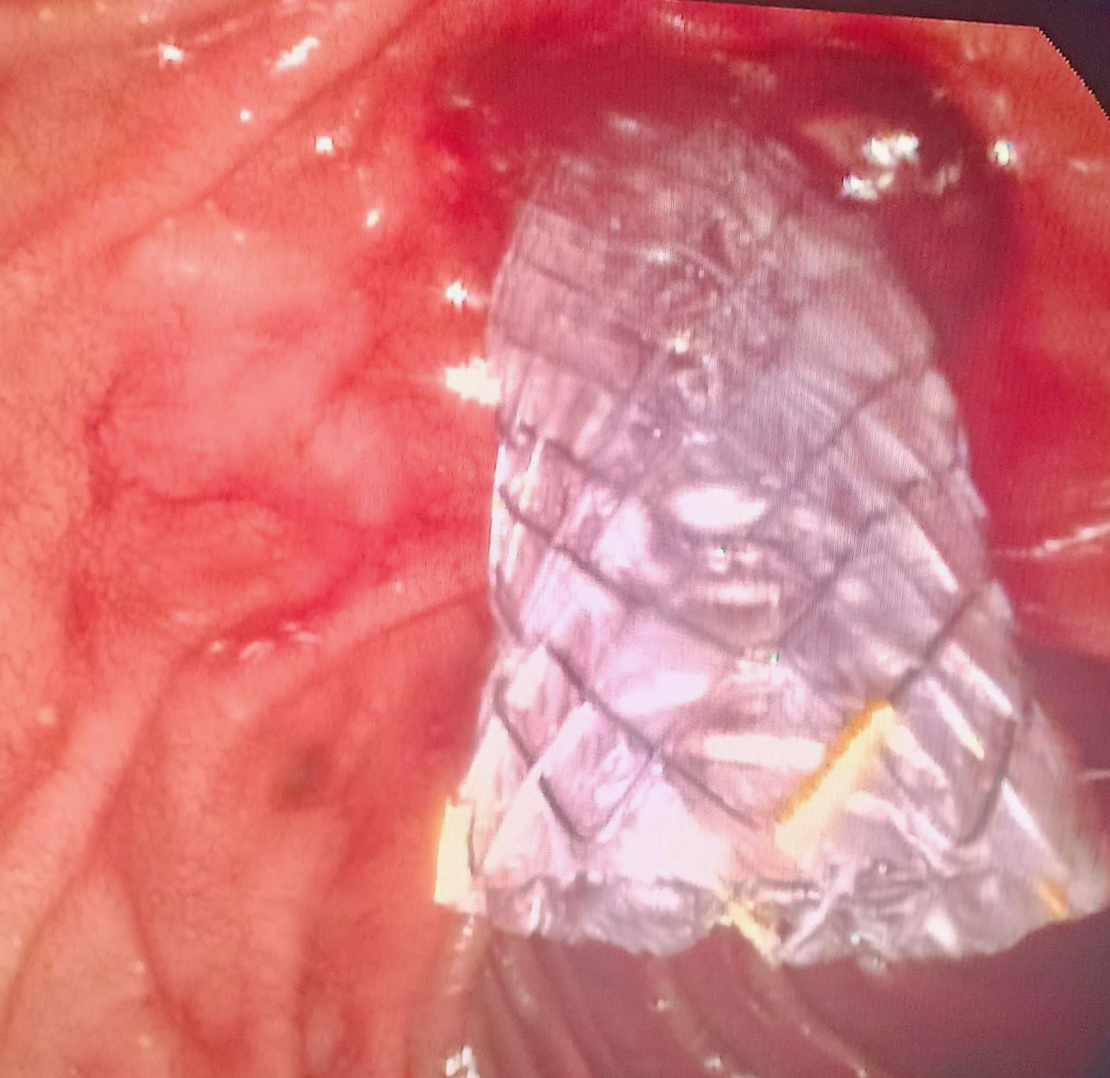

La prótesis Ultraflex esofágica parcialmente recubierta es muy útil para tratar perforaciones en el esófago como comentamos en este caso. https://t.co/QtFXQX8Rpd